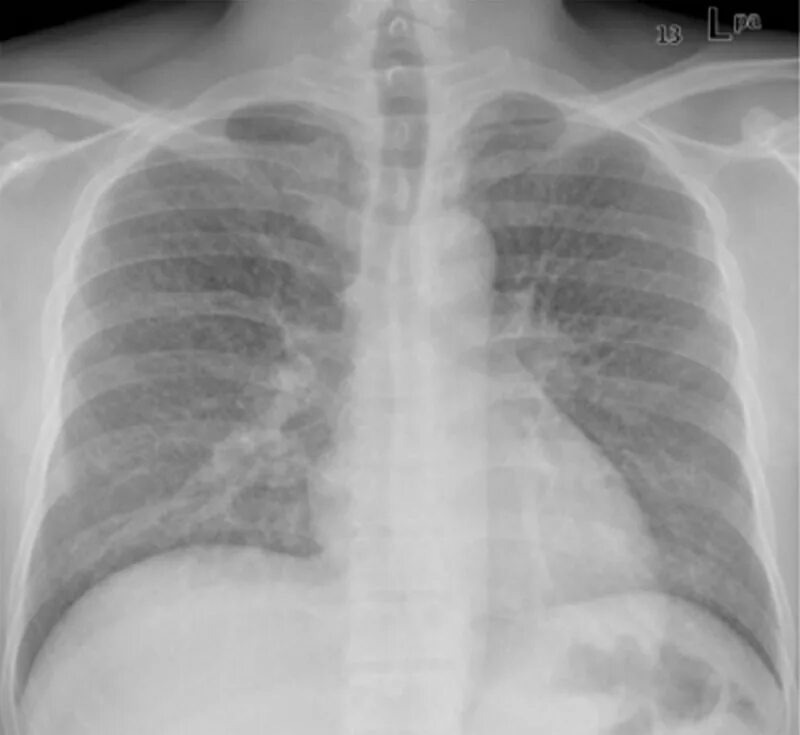

Почему метастазы в легких